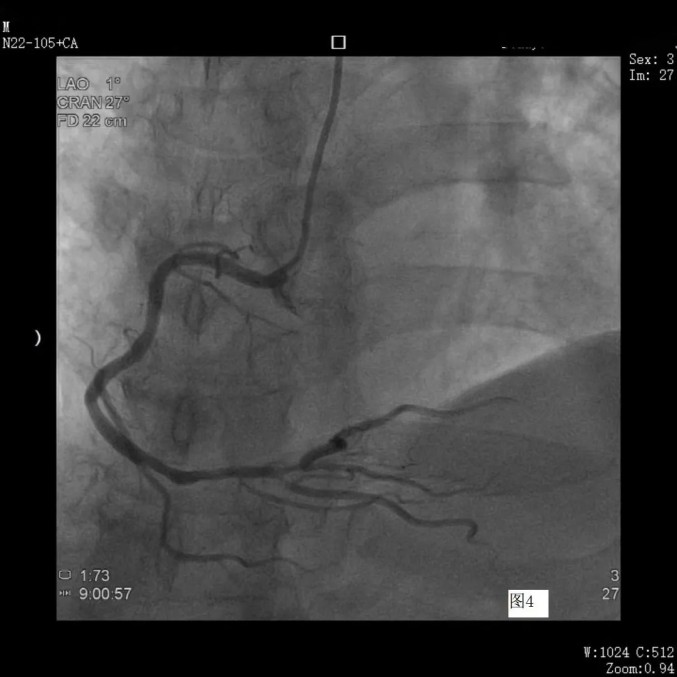

冠脉造影见右冠支架术后良好

左侧冠脉与上次狭窄程度无变化

两个手术先后实施,用时不到一个小时,为下一步治疗指明了方向。由于手术只是在手腕处穿刺一个小口,张先生感觉跟平常静脉输液无异,可自由下床活动,也无其他不良反应,一家人对此次手术非常满意,称赞这次造影真是“一举两得”。